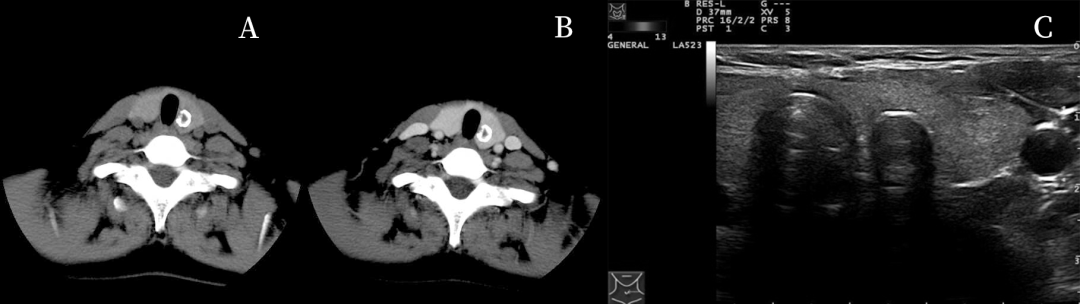

左侧甲状腺结甲环状钙化 医学百科网 | YxBaike.Com

A 超声横切见弧形钙化,钙化后方声衰显著,相应结构显示不清;

B CT平扫见环形钙化,壁厚薄较均匀;

C 增强后环内无强化,相对平扫,甲状腺与环内密度差扩大。